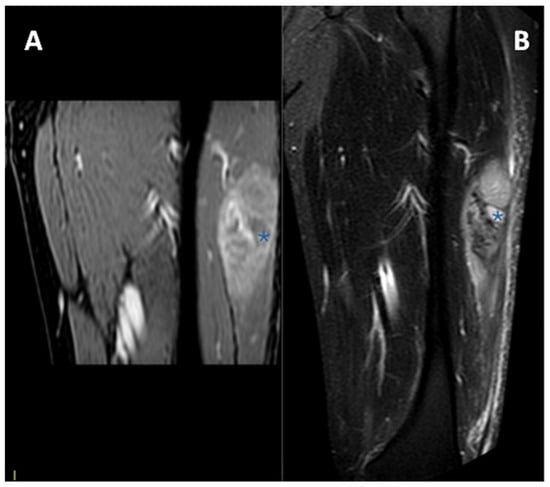

1.1. General Characteristics, History and Epidemiology

1.3. Imaging and Clinical Features

1.3.2. Magnetic Resonance Imaging

3.4. MRI Features

3.4.1. General MRI Features

3.4.2. Peritumoral Edema

3.4.3. Other MRI Features